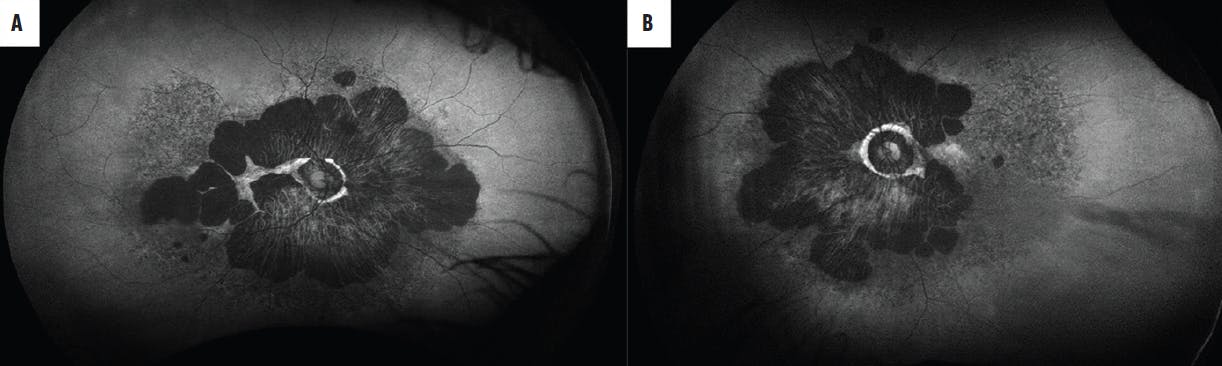

The ocular examination revealed BCVA of hand motion OD and 20/60 OS. Slit-lamp examination revealed lenticular changes in each eye. Dilated examination and retinal imaging revealed marked chorioretinal atrophy in the macula extending into the midperiphery, vascular attenuation, pigment plaques, retinal pigment epithelium (RPE) mottling, and optic nerve pallor (Figure 1).

<p>Figure 1. The fundus photographs of our patient’s right (A) and left (B) eyes showed marked macular atrophy, extensive chorioretinal atrophy, vessel attenuation, peripapillary changes, and pigmentary changes.</p>

Figure 1. The fundus photographs of our patient’s right (A) and left (B) eyes showed marked macular atrophy, extensive chorioretinal atrophy, vessel attenuation, peripapillary changes, and pigmentary changes.